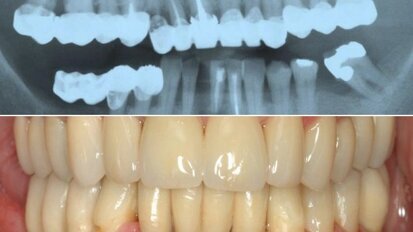

На 8 и 9 ноември 2014 г. в Атина предстои двудневен теоретично-практически курс по ...